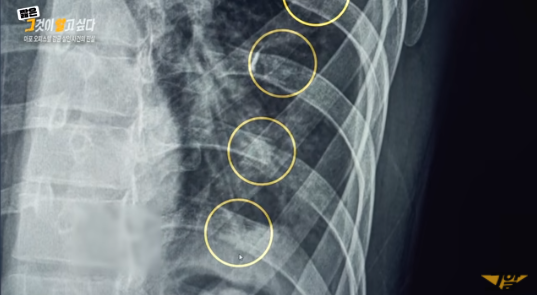

경찰은 지난 6월 13일 오전 6시 경 오피스텔에 나체로 숨져 있는 피해자를 발견했고, 안모(21)와 김모(21)을 긴급 체포했다. 경찰 조사 결과 사망 당시 피해자의 몸무게는 34kg의 극심한 저체중 상태였으며, 사인은 폐렴·영양실조 등이었다.